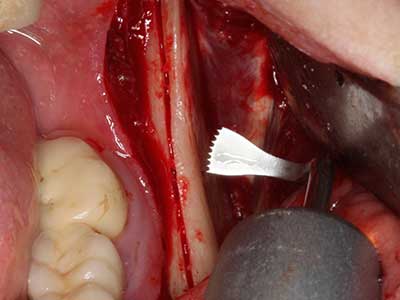

Si es preciso realizar intervenciones quirúrgicas en las que el hueso está en contacto directo con estructuras sensibles, como son los vasos sanguíneos o los nervios, los instrumentos rotativos presentan un enorme potencial de provocar lesiones iatrogénicas. Así, precisamente en la representación de nervios después de una lesión iatrogénica, o en el transcurso de la lateralización de un nervio para resecciones, reconstrucciones o incorporación de implantes, los equipos piezoeléctricos pueden resultar muy útiles para preparar la tapa ósea y retirar las partes de tejido duro cercanas al nervio (fig. 17-20). Por lo general, un ligero contacto del cordón nervioso con el inserto piezoeléctrico no tiene consecuencia alguna; ahora bien, un procedimiento poco cuidadoso con movimientos tipo sierra o piezas de trabajo sobre la base ósea aún existente puede provocar lesiones nerviosas temporales o incluso permanentes. Con todo, el riesgo de sufrir una lesión de este tipo se considera significativamente inferior que en los casos en los que se utilizan sierras y fresas (Pereira, Gealh et al. 2014).